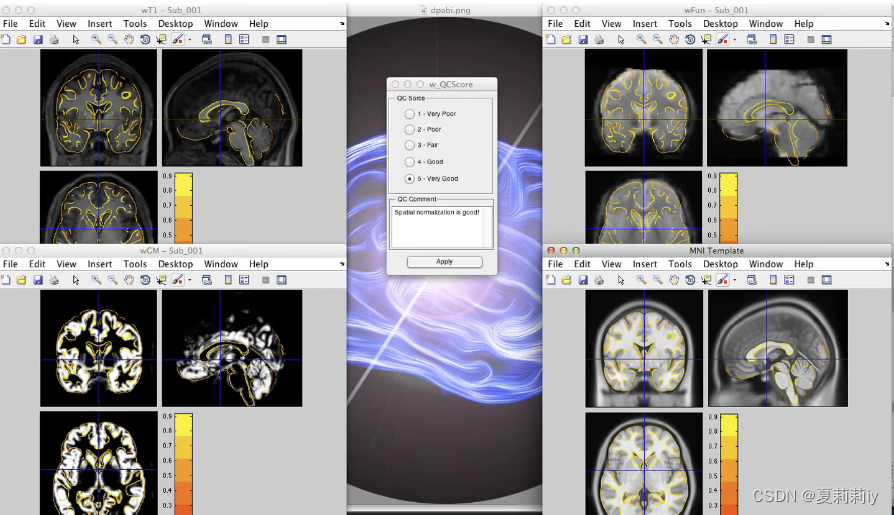

(4)QC:Normalization

①黄色的线条是白质灰质的边界

②在中间QC Comment可以给对于白质灰质分界判断好坏的分数

③第二次点QC:Normalization的时候会生成分数框